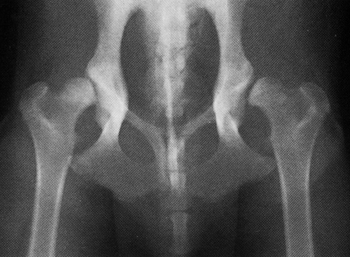

Les mâles ne doivent pas souffrir du dos (hernie discale,

arthrose, traumatisme du bassin…), ni des hanches (dysplasie, arthrose…),

ce qui compromettrait le chevauchement.